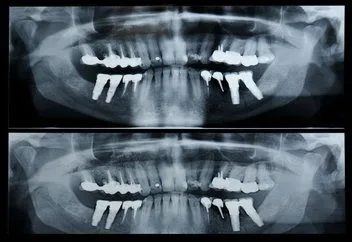

Panorex

panorex x-ray

A panorex is a very impressive piece of imaging machinery in that it is capable of identifying many issues and structures that a normal x-ray is not. Initially you will sit in a chair with your chin on a small ledge. Once positioned in the machine, it will rotate around your entire head taking a full 360 degree view of the teeth, head, sinuses and bones.

The ability to view the full structure of your head as a whole is very informative to the dentist. It will allow us to see any potential problems and make sure that everything is functioning as it should be. The panorex is capable of viewing specific types of structural problems, infections or asymmetry among many others.